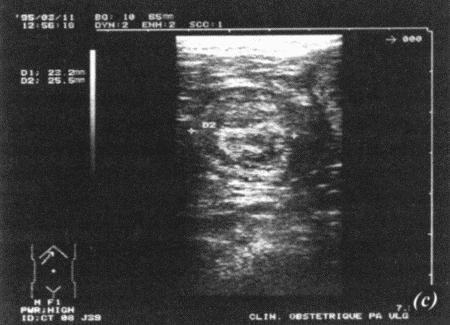

Фиг. 17.2.

Ультрасонографическое изображение (а, b) нормальная беременность (38 дней) в результате естественной вязки; (с) резорбция эмбрионов, индуцированная каберголином в сочетании с простагландином